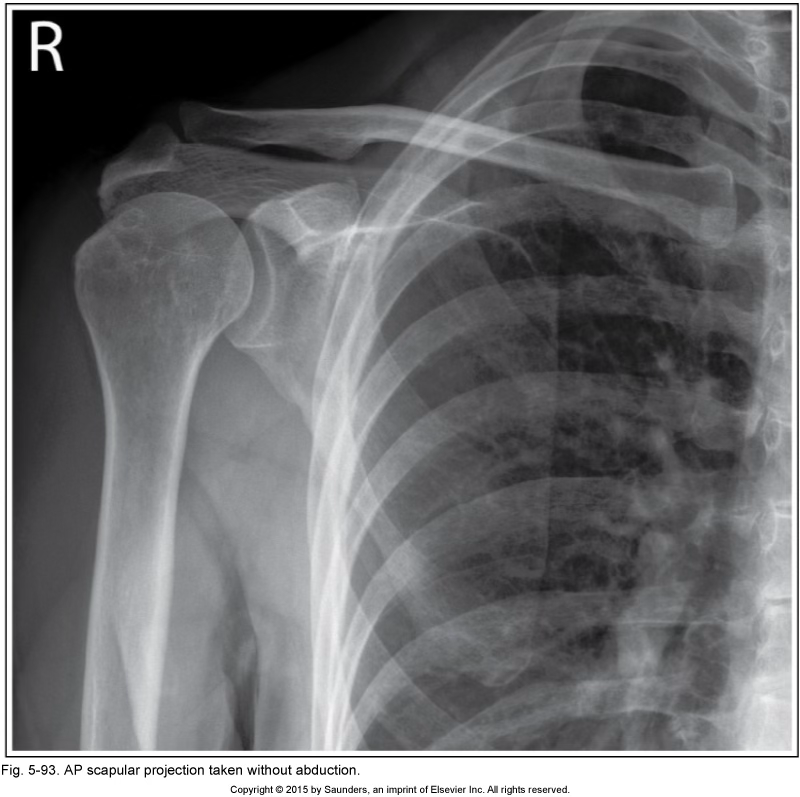

AP scapula

no hand abduction